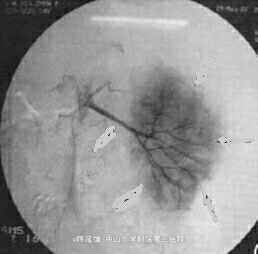

影像学表现:CT平扫,左肾区巨大、不规则形包块,其后内见片状低密度坏死灶,右内近边缘处另见2枚高密度影,肿块最大层面直径约13.2 cm×12.2 cm,周围结构受压移位,部分结构与肿块界限欠清。DSA提示:相当于左肾位置似见左肾动脉、左肾轮廓及其动脉的正常分支,未见明显肿瘤血管,腹主动脉其他部位未见明确动脉分支向“假肾影”供血。DSA诊断肾细胞癌证据小足,遂放弃介入治疗。左肾区肿块穿刺活检病理:小细胞性恶性肿瘤,考虑为恶性淋巴瘤,免疫组织化学染色CD20普遍阳性,支持B细胞淋巴瘤。行标准B细胞淋巴瘤化疗。